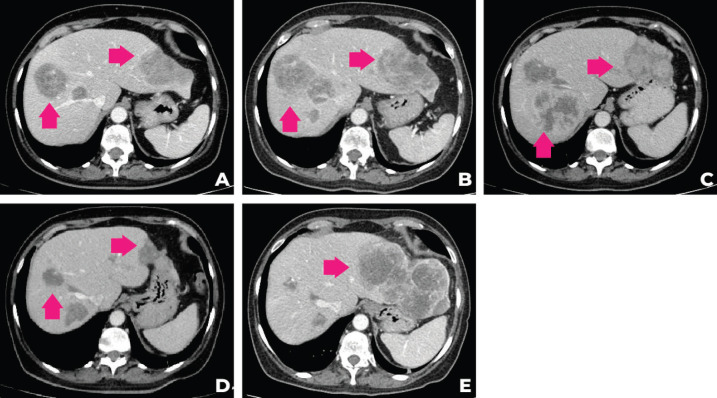

考慮到患者的臨床病程和多基因檢測包的結果,MTB 第二次會議討論建議進行腫瘤靶向藥物基因檢測850的遺傳咨詢,并開始使用他拉唑帕尼進行全身治療。 遺傳咨詢后,進行了 33 個基因組,包括與結腸癌、婦科癌和結直腸癌相關的基因(APC、ATM、AXIN2、BARD1、BMPR1A、BRCA1、BRCA2、BRIP1、 CDH1、CHEK2、DICER1、EPCAM、GREM1、MLH1、MSH2、MSH3、MSH6、MUTYH、NBN、NF1、NTHL1、PALB2、PMS2、POLD1、POLE、PTEN、RAD50、RAD51C、RAD51D、SMAD4、SMARCA4、STK11、TP53)的基因檢測。在所有檢測的基因中沒有任何一個被發(fā)現(xiàn)任何相關的突變或變異。 2021 年 9 月,經(jīng)過 talazoparib 治療 3 個月后,觀察到腹痛和肝臟部分反應的臨床改善。 在提交本病例時(2021 年 12 月),腫瘤反應正在進行中。 圖 2 描繪了患者主要放射學發(fā)現(xiàn)的總結,圖 3 描繪了患者演變的時間表。

圖 2:患者計算機斷層掃描在不同時間段的演變。 (a):2020 年 12 月的 CT,(b):2021 年 4 月,(c):2021 年 6 月,(d):2021 年 9 月,(e):2021 年 12 月